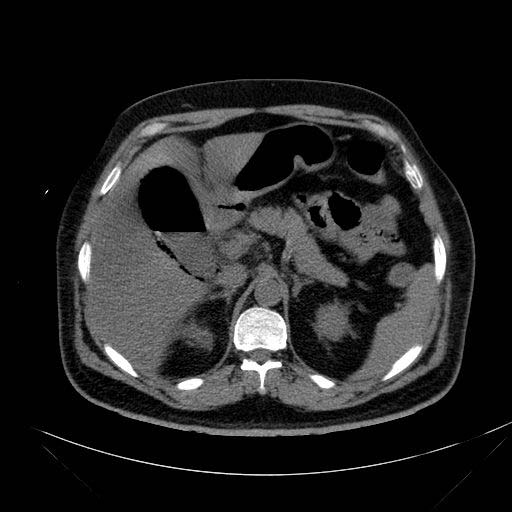

On examination he was febrile with temperature of 38.8c. His blood pressure was (80/40 mmHg), pulse was 120 and respiratory rate was 28/min. His abdomen was slightly distended with remarkable tenderness and rigidity over the right hypochondrium. Murphy's sign was positive. His ECG was normal and his blood gas analysis showed slight metabolic acidosis. His hemoglobin was (13 g/dl). Urea and electrolytes, liver function test and serum amylase were within normal values. His erect chest X Ray excluded free air under the diaphragm (Figure 1). After initial fluid resuscitation he had abdominal CT scan (Figure 2A & B) which showed a distended thickened wall gallbladder containing air within its wall and lumen with air-fluid level. There was also a curvilinear hyper density in relation to the gallbladder wall, with gallbladder wall calcification and pericholecystic fat stranding extending to the region of the hepatic flexure. There was no obvious evidence of gallstones seen and no evidence of intra-or extrahepatic biliary dilatation. The CT scan findings were consistent with non-calculus emphysematous cholecystitis. The patient did well and discharged on the 7 th post cholecystostomy day. The cholecystostomy tube was removed after 6 weeks and he remained symptoms free on follow up for more than a year.

Abdominal CT scan is now considered the primary imaging modality to confirm acute emphysematous cholecystitis, as it is the most sensitive and specific imaging modality for identifying gas in the gallbladder lumen or wall. (18,19) CT scan demonstrates emphysematous changes in the gallbladder wall that are diagnostic of this condition and is highly sensitive for tiny bubbles of air which may not be seen on ultrasonography. It can also provide precise information regarding the location and extent of air and fluid collections, such as extension into the pericholecystic tissues and the hepatic ducts. Gas in the peritoneum indicates perforation. (20) Magnetic resonance imaging (MRI) can provide extensive information on intramural necrosis as well as intraluminal gas. Gas in the gallbladder lumen and wall appear as signal void areas. (21) Characteristic MRI findings of emphysematous cholecystitis are numerous floating signal void bubbles in the upper dependent portions of the gallbladder (22).